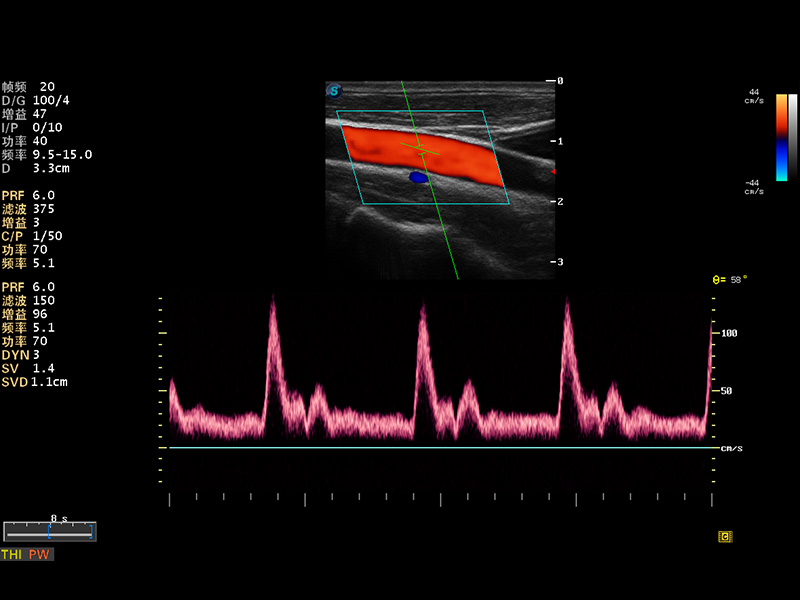

多波束形成器